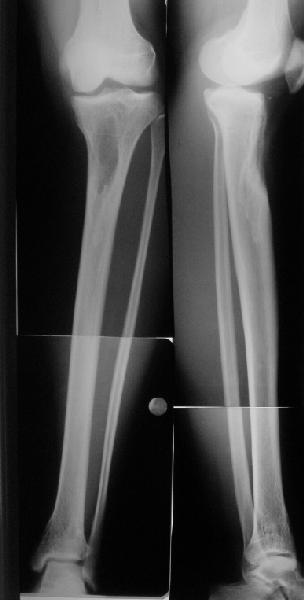

Коллеги из детского отделения направили 18-летнюю студентку с варусно-рекурвационной деформацией проксимального отдела голени.

Жалобы у нее на появившиеся боли в колене при нагрузках. Признаков воспаления не было и нет, опухолевого роста также. Природа дефекта в области бугристости не очень понятна. Дополнительно сделали КТ и боковой снимок в максимальном разгибании - все в приложении.

По-поводу деформации - Вы имеете дело с епи-метафизарной деформацией, скорее всего по причине преждевременного частичного закратия проксимальной зоныы роста большеберцовой кости.

Рекурвации в коленном суставе нет, есть рекурвационная деформация проксимальной части голени.

За точку отсчёта при планировании коррекции надо взять латеральный снимок в максимальном стрессе на разгибание. Остеотомию необходимо произвести тот час дистальнее места прикрепления собственной связки надколенника.(очень важно)

Ориентировачно на боковой проекции угол между тибиальным плато и анатомической осью тибии на передне-боковой проэкции должен быть порядка 90 градусов, а на боковой 80, кроме того на боковой проэкции при выпрямленном колене передний кортекс большеберцовой кости должен находиться на одной линии с передним кортексом бедренной кости.